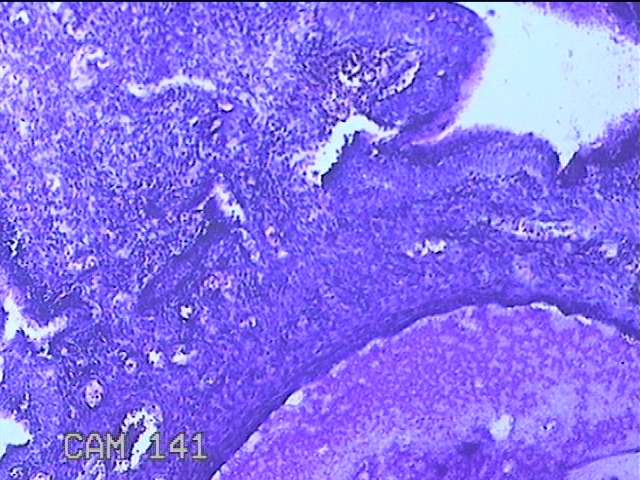

宫颈赘生物

性别

女

年龄

49岁

临床诊断

人乳头瘤病毒感染

一般病史

宫颈HPV阳性TCTLSLL

标本名称

大体所见

灰白粉红色肿物1.2x0.8x0.2cm两个,表面光滑。

图3